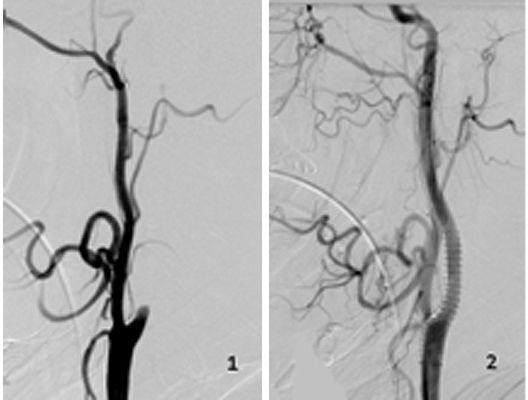

Das Beispiel zeigt die angiographischen Bilder einer Patientin, bei der es zu einer Sehstörung gekommen war. Die Ursache war ein großes Aneurysma der Halsschlagader an der Schädelbasis (Bild 1). Bild 2 zeigt die Lage des Aneurysmas hinter dem Auge. Durch den Druck des Aneurysmas auf den Sehnerv war es zu der Sehstörung gekommen. Die Patientin wurde mit einer speziellen Gefäßprothese versorgt, welche über eine Punktion der Leistenarterie in die Halsschlagader eingesetzt wurde (Bild 3). Bei der Kontrolle nach 6 Monaten zeigte sich ein vollständiger Verschluss des Aneurysmas (Bild 4). Die Sehstörung hatte sich vollständig zurückgebildet.